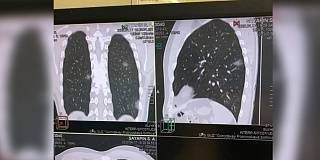

КТ легких при коронавирусе: когда нужно делать?